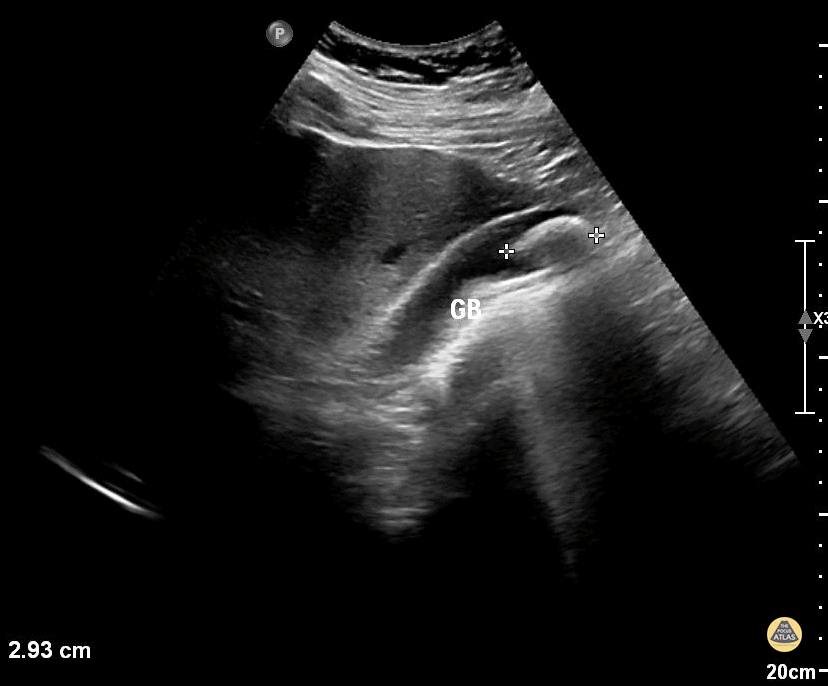

Peds-Biliary - Cholelithiasis

15 year old with right upper abdominal pain No other history On examination, tenderness over right upper/rebound tenderness as well USG abdomen revealed the above image Contributor: Dr Vanitha American Mission Hospital